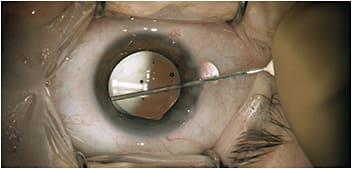

The surgeon performs the transzonular TriMoxi+vancomycin injection using a 27-gauge hydrodissection cannula.

COURTESY: JAMES S. LEWIS, MD